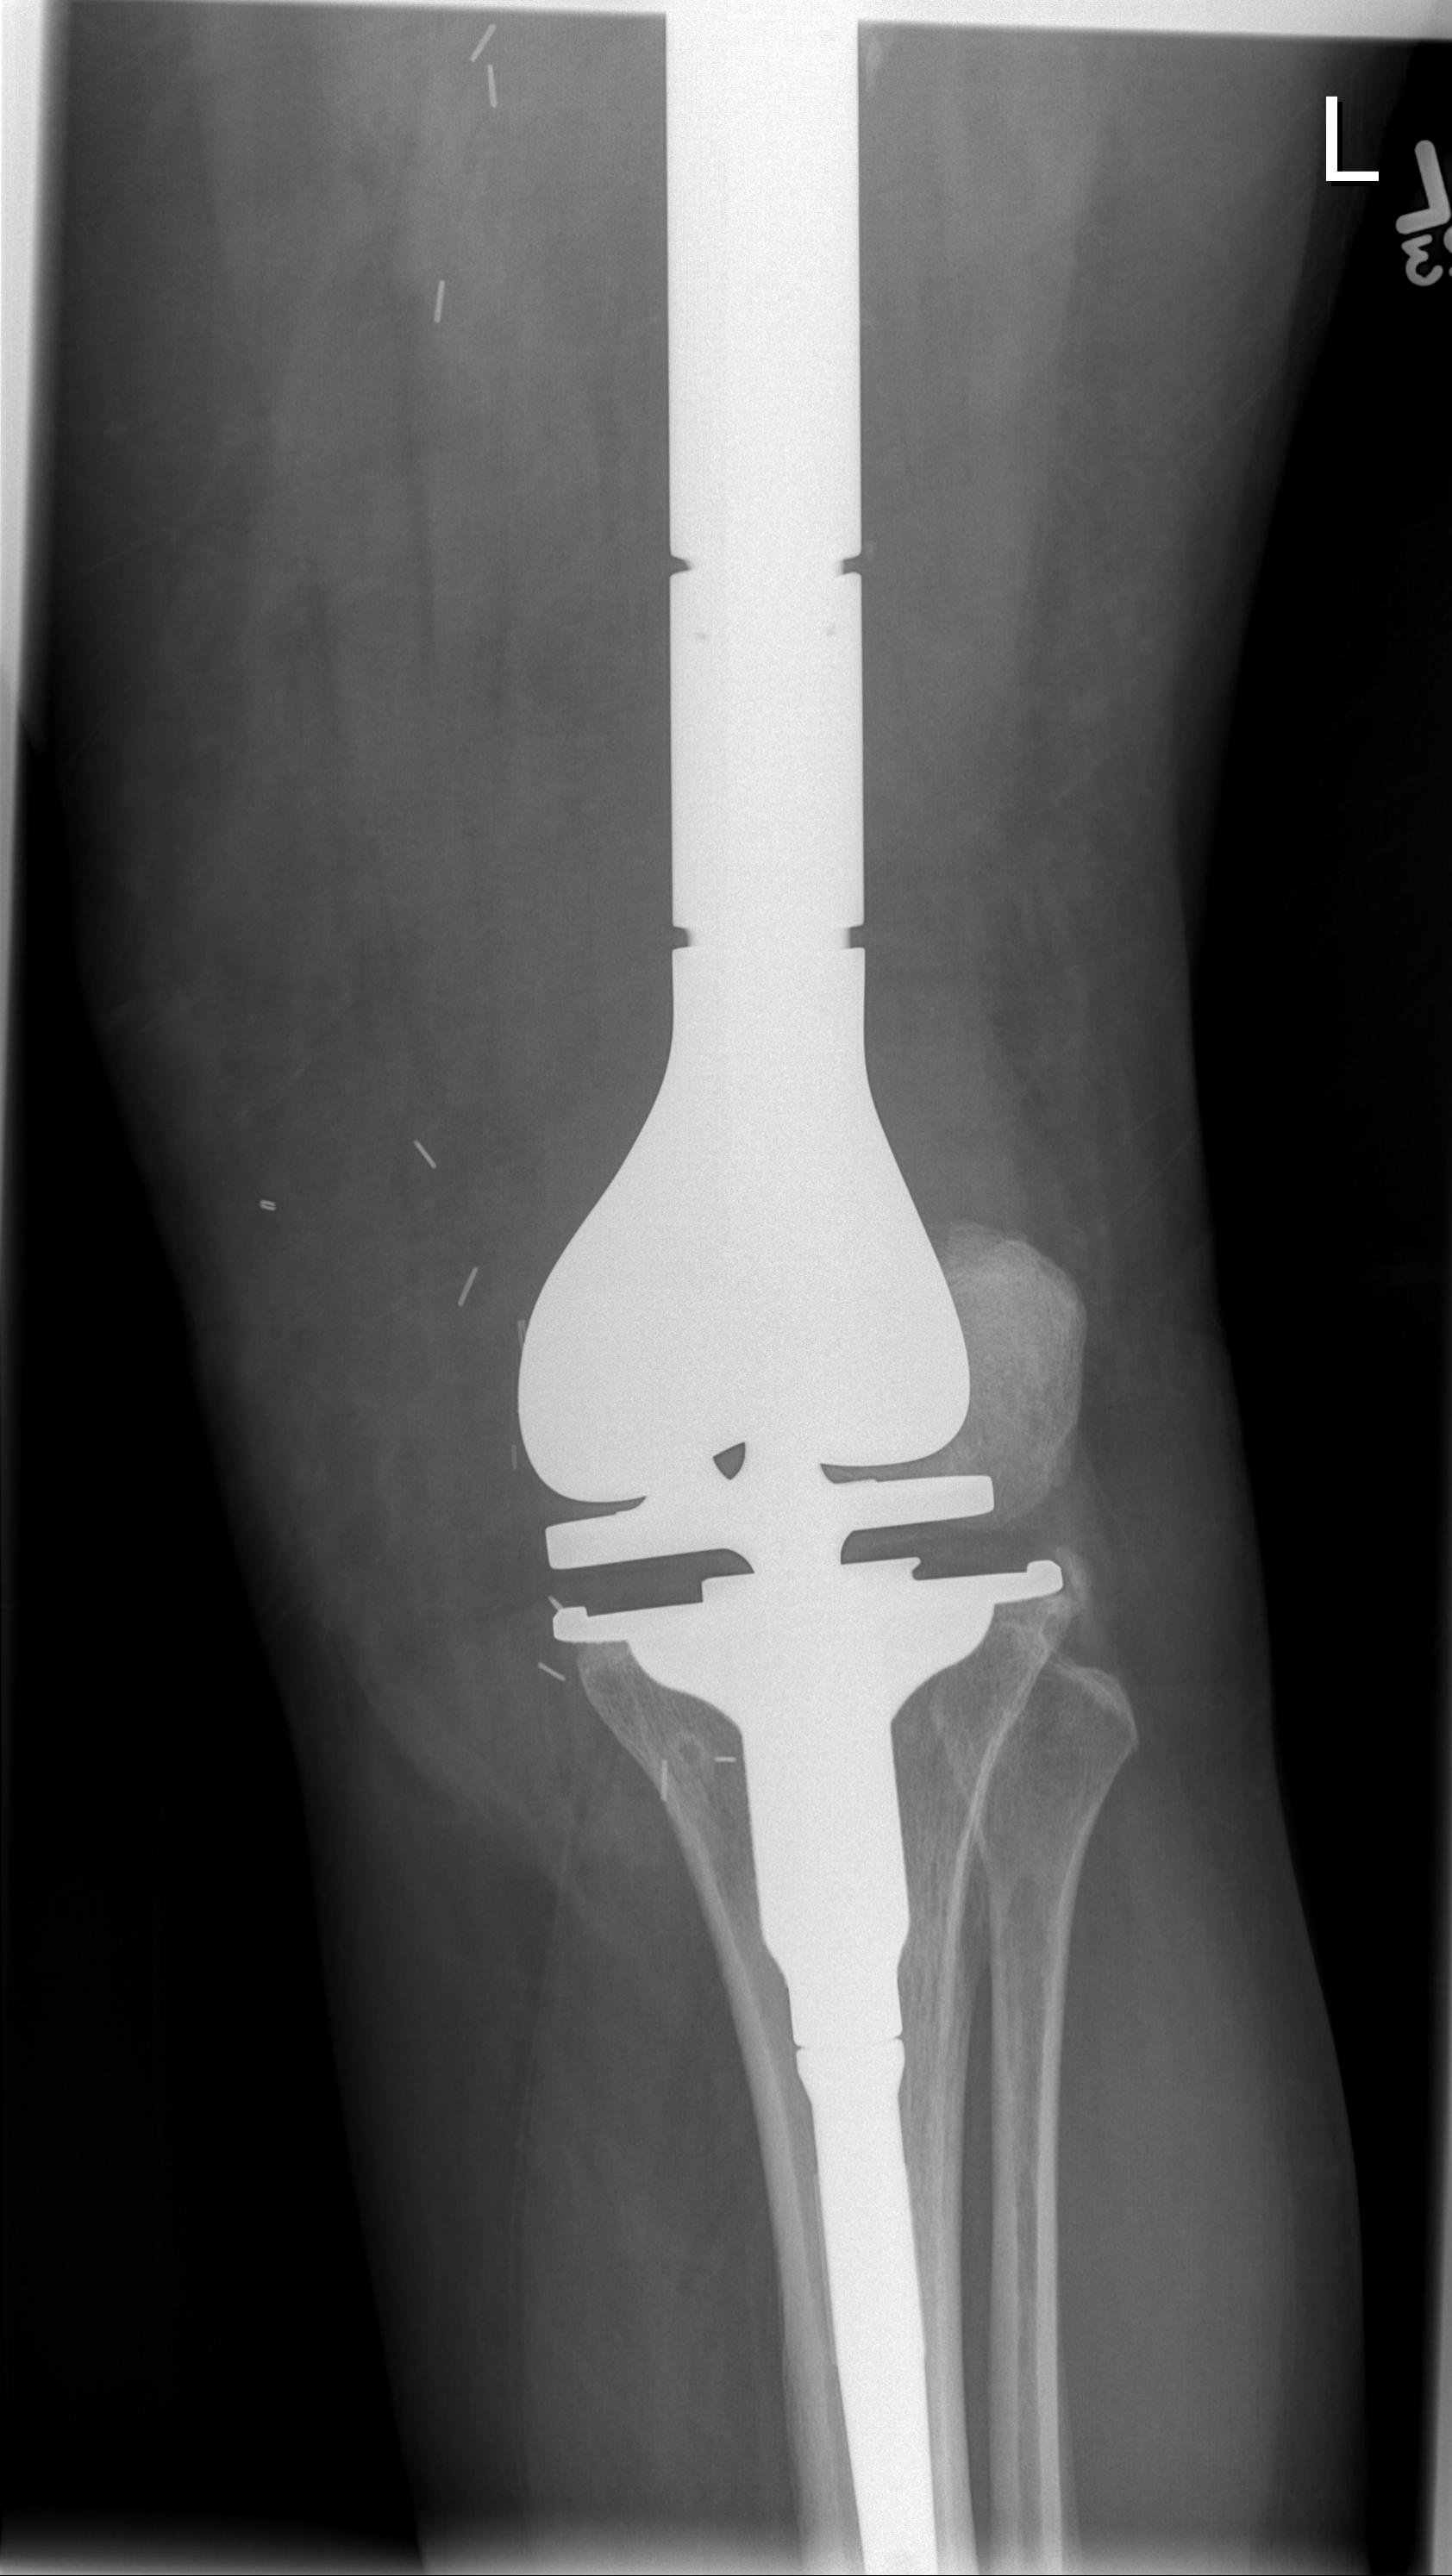

Post distal femoral osteosarcoma resection

Post proximal tibial osteosarcoma resection

Results

- cemented megaprosthesis for high grade osteosarcoma around the knee

- 108 patients with average age 25

- 5 year prosthesis survival 78%

- 8 year prosthesis survival 55%

Sadek et al Ann Surg Oncol 2023

- modular endoprosthesis for osteosarcoma of the distal femur

- 82 patients

- 5 year prosthesis survival 68%

- 10 year prosthesis survival 52%

- aseptic loosening commonest complication 19.5%

- deep infection 15.9%

Ebeid et al Ann Surg Oncol 2023

- modular endoprosthesis for osteosarcoma of the proximal tibia

- 55 patients

- 5 year prosthesis survival 82%

- 10 year prosthesis survival 62%

- aseptic loosening commonest complication 14.5%

- deep infection 14.5%

- periprosthetic fractures 16%